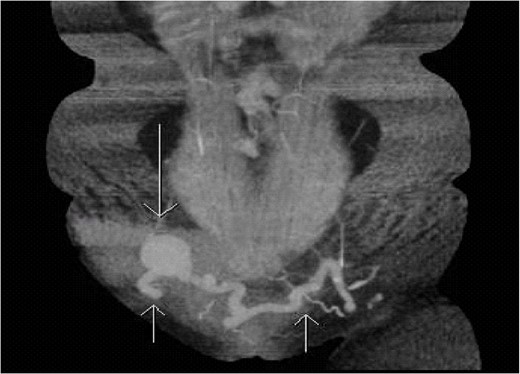

On CT and ultrasound imaging of the abdomen, the patient was found to have an anomalous venous connection between the left and right saphenous veins. The connection traversed across the anterior abdominal wall and contained an aneurysmal segment close to the right saphenofemoral junction that was 3.6 cm in diameter and was partially thrombosed (Figs 1 and 2). The patient had a duplex ultrasound on hospital day one that showed the femoral veins to be patent bilaterally. Systemic anticoagulation was started with warfarin. On hospital Day 2, the patient’s pain improved and she was subsequently discharged on warfarin therapy before her INR was therapeutic with an outpatient lower extremity venous duplex to ensure no further progagation of the thrombus.

Coronal section of CTA of the abdomen/pelvis capturing the anomalous connection between the left and right greater saphenous veins with an aneurysm near the right saphenofemoral junction. Short arrows pointing up shows the tortuous connection of the greater saphenous veins. Long arrow pointing down demonstrates an aneurysm in the anomalous saphenous vein connection.